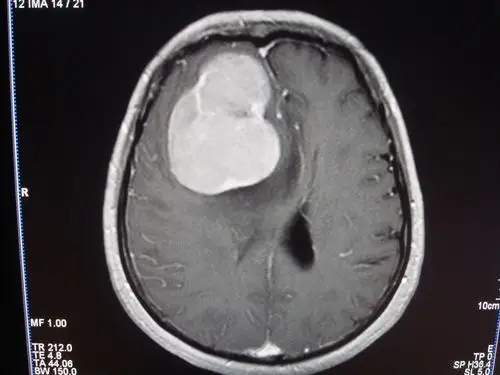

脑膜瘤是神经外科中最常见的良性肿瘤,顾名思义,脑膜瘤和脑膜关系密切

右侧额顶叶占位脑膜瘤可能